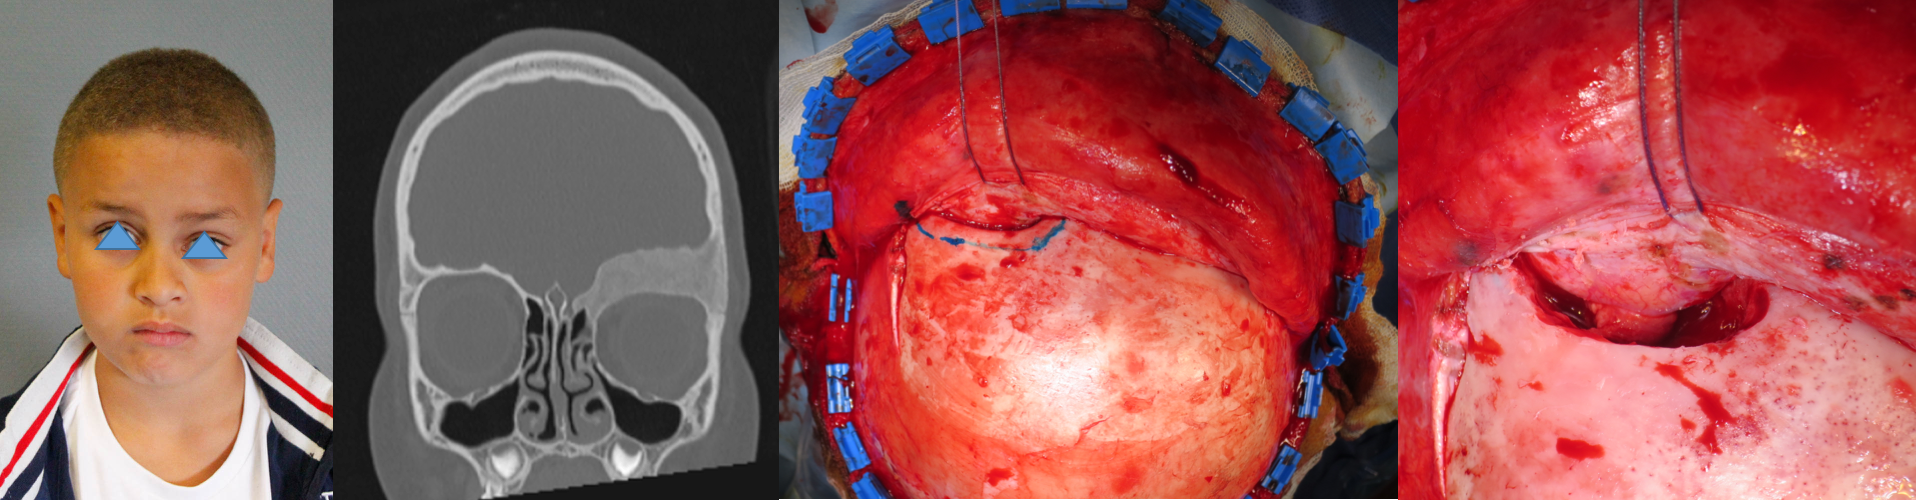

les sarcomes

divers types de sarcomes peuvent affecter la voûte crânienne. ce sont des lésions rares, pour lesquelles la chirurgie est le plus souvent nécessaire, dans un but anatomo-pathologique ou d’exérèse la plus complète possible, y compris le périoste et la dure-mère. la résection totale est cependant souvent limitée par l’infiltration des sinus veineux duraux.